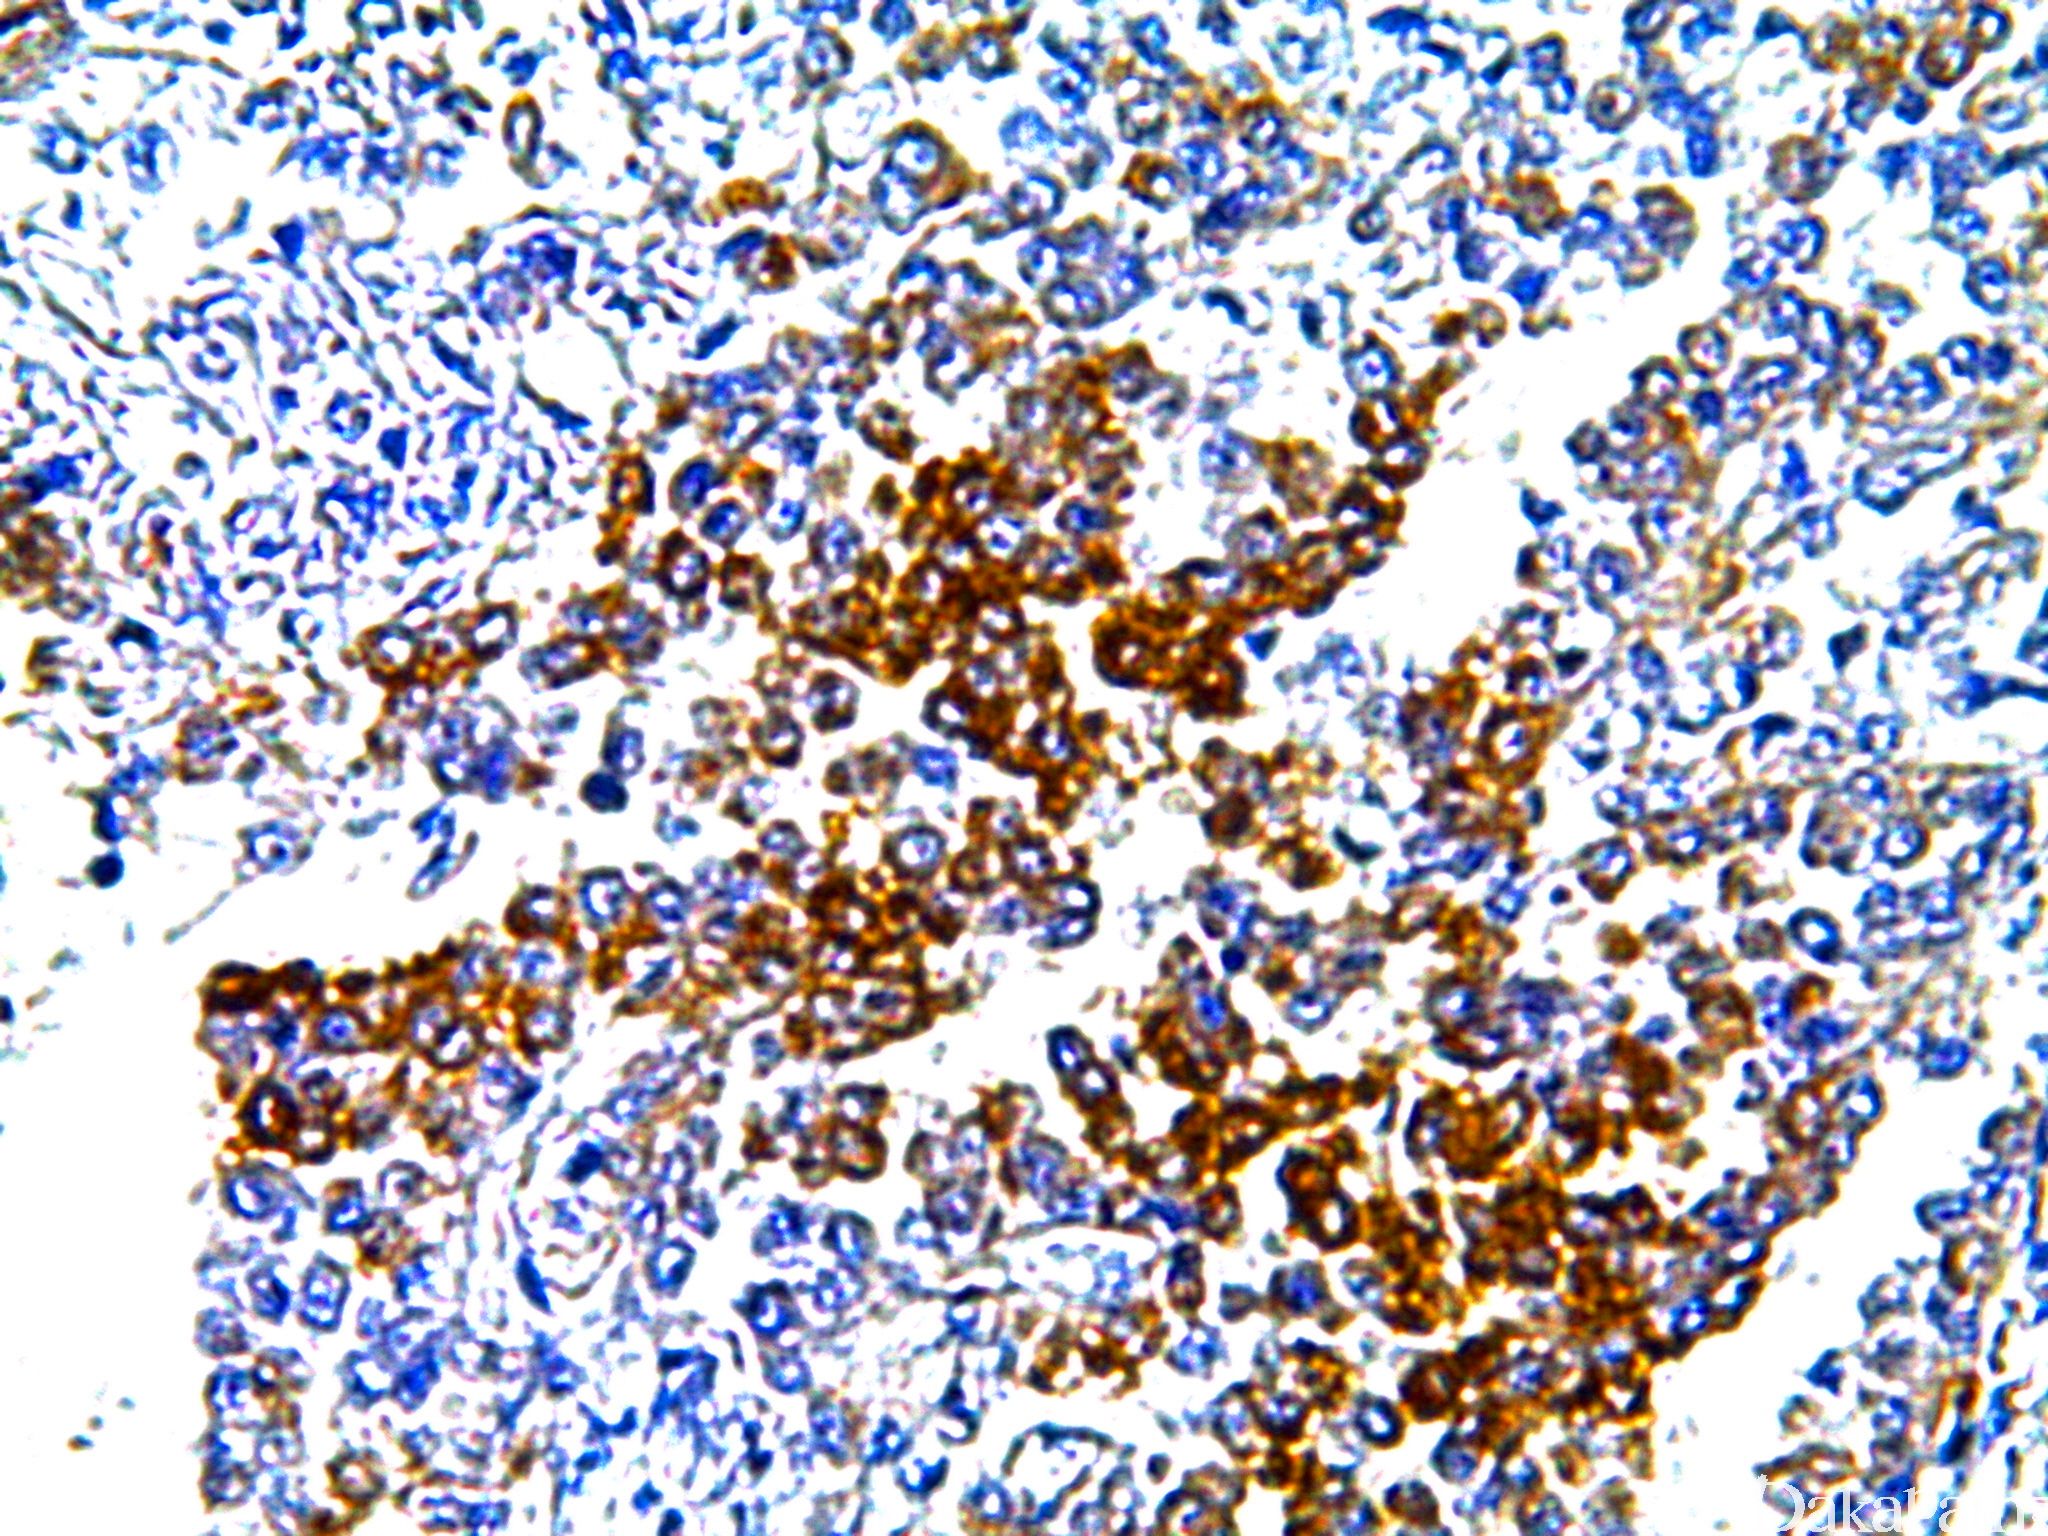

GLUT1

信号定位: 胞膜

几乎全部阳性(≥95%的病例阳性): 透明细胞肾细胞癌、甲状腺癌显示胸腺样分化、甲状腺间变性癌、神经纤维瘤、肺鳞状细胞癌

通常阳性(<95%,≥75%的病例阳性): 透明细胞乳头状肾细胞癌、神经鞘膜瘤,NOS、间皮瘤,NOS、肾细胞癌、乳腺导管原位癌、甲状腺乳头状癌、神经束膜瘤、甲状腺低分化癌、输卵管腺癌、间皮瘤,双向分化

经常阳性(<75%,≥55%的病例阳性): 子宫内膜腺癌 I-II 级、子宫平滑肌肉瘤、上皮样间皮瘤、甲状腺滤泡性癌、乳腺浸润性癌,非特殊类型